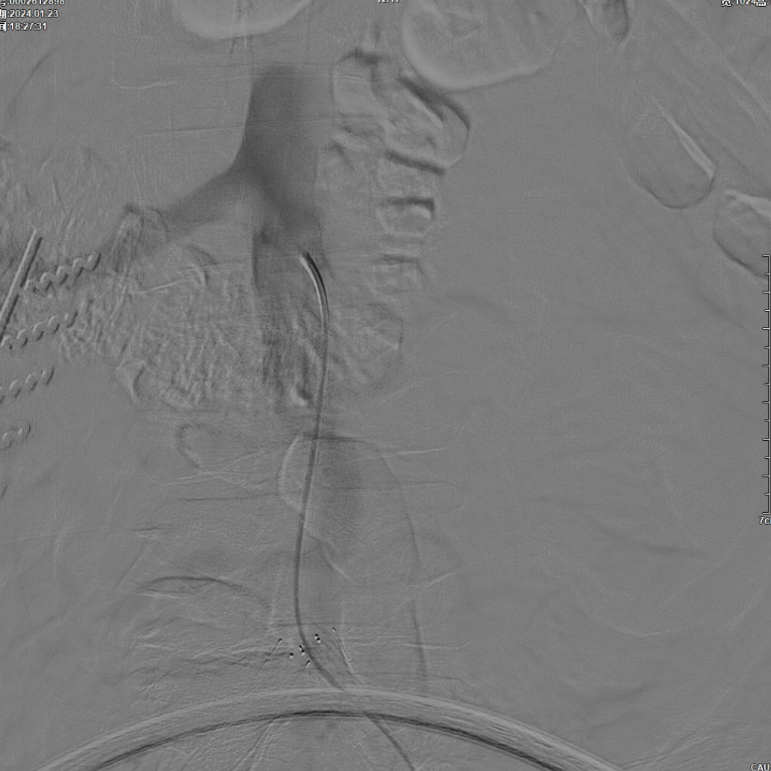

首先使用14mm球囊进行初步扩张,鉴于腹主动脉直径约15mm,最终选用16mm球囊进行扩张。

当扩张压力达10 ATM时,患者出现轻微疼痛,遂停止扩张。扩张前需将左侧导丝撤出,扩张后重新置入并确认导丝位于支架内。

CERAB技术关键点二:先用14mm×40mm球囊分别扩张双侧髂肢的腹主动脉段。

再用8mm球囊对双侧髂支腹主动脉段行对吻扩张,以确保双侧髂支与腹主动脉覆膜支架腔内获得良好的贴壁形态,最大程度减少空腔,降低远期再狭窄发生率。